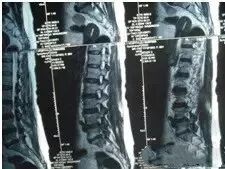

一张标准的胶片,医生最终的着眼点往往只在2-3mm的致病处,只有拍清楚细节部分,医生才能够给出准确的答复,所以分格的片子应该每4-6小格拍一张,不能图省事整张拍摄,那是自己糊弄自己啊,为了您的病情,辛苦一点吧。

对好焦距的重要性,是否对好焦的标准是能否看出做检查的日期。